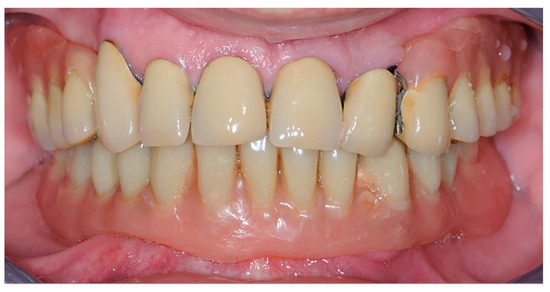

2.1. First Step: Complete Fixed Rehabilitation

2.2. Second Step: From FDP to Implant-Supported Overdenture